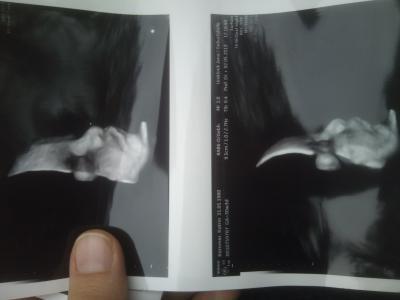

Pummelsche

Süß oder?

Oh wie süß , wunderschön Gut gemacht

Die Aufnahmen sind klasse!!!